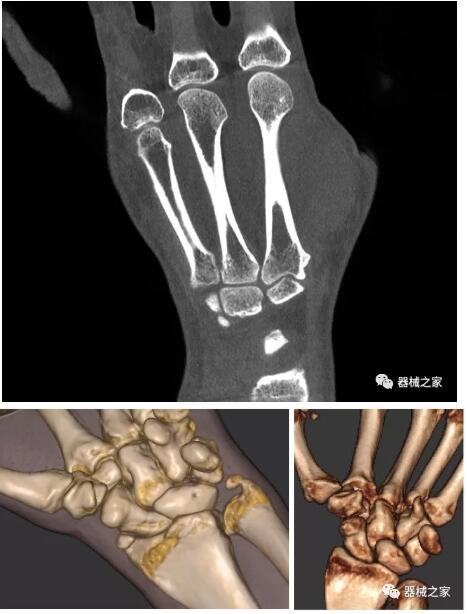

另外一款被稱為世界上最小的CT,它的重量僅300磅,不僅能夠掃查足部,還可以檢查膝蓋和上肢等。

與上面介紹的CT一樣,它同樣具有輻射低、占地空間小(23*36)的特點,隨開隨用(支持直接接入墻上的插座)。

這款CT使用非常方便,通過上下移動保持與患者的手臂或者雙腿齊平,掃描快速,僅需要30秒左右就可以完成掃查。

以上介紹的CT均來自國外同一家公司,這些CT均配置了可視化軟件,可以進行切片、3D重建以及大型CT附帶的所有典型的操作功能。

以下是這些“特立獨行”的CT所拍出來的圖像: